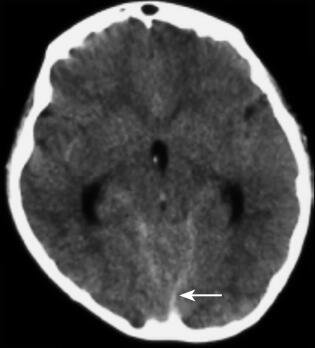

诊疗经过:入院后行腰椎穿刺术,连续留取3管脑脊液,均为淡红色血性脑脊液,脑脊液化验结果除外中枢神经系统感染。2010年10月28日晚19时40分患儿站立中诉腿疼,平卧后再次出现抽搐,表现为口吐白沫、双手握拳、双上肢屈曲、颈部强直,并有意识障碍。予吸氧、镇静止惊、改善脑水肿等对症治疗,仍反复抽搐多次。急诊行颅脑CT检查,示脑室及蛛网膜下腔少量出血(图3)。遂由儿内科转神经外科治疗。转科后行全脑全脊髓血管造影提示:T11~L2脊髓血管畸形(图4)。遂于2010年11月10日在全麻下行T11~L2脊髓畸形血管团切除+椎板扩大成形+硬膜修补术。术后给予脱水、抗炎、止血、补液、支持、神经营养、激素等治疗后患者意识逐渐转清,未再抽搐,病情稳定出院。

图3 第三次颅脑CT检查(2010年10月28日):脑室及蛛网膜下腔少量出血(箭头)